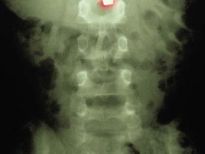

Bu röntgenler gerçek!

Bu röntgenler gerçek! galerisi resim 1

İki çatalı, bir tükenmez kalemi ve diş fırçasını yutmuş bir hasta.